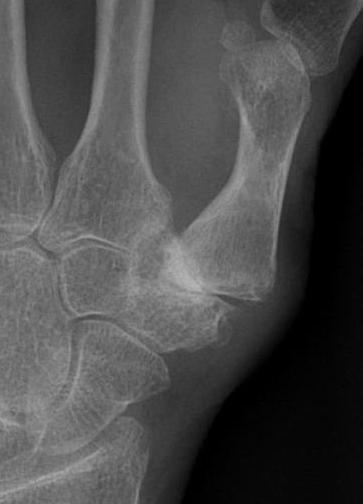

Eaton Classification

| Stage I | Stage II | Stage III | Stage IV |

|---|---|---|---|

|

Xray normal Synovitis |

Joint space narrowed Mild subluxation |

Severe joint space OA Radial subluxation of joint |

CMC + STT OA |